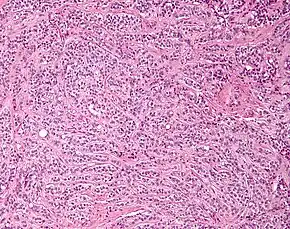

| Micrograph of a Sertoli cell tumour. H&E stain. | |

Microscopy and immunohistochemistry are the only way to give a definitive diagnosis, especially when there is a suspected seminoma.[3]